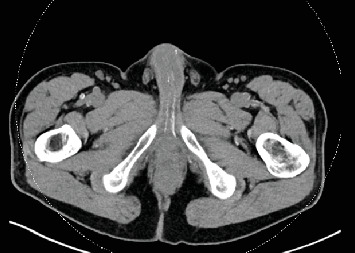

COVID-19大流行影响了全球数百万人。虽然主要被认为是一个呼吸过程,但可能有直接和间接的泌尿系统后果,但很少讨论。本病例报告描述了一例严重感染COVID-19导致肾和肝移植的患者。康复后,患者被发现有新发勃起功能障碍和佩罗尼病。我们怀疑导致肝肾功能衰竭的全身炎症和血管病变也导致了严重的动脉粥样硬化性勃起功能障碍。此外,俯卧位可能代表了Peyronie病的医源性病因。这个独特的病例表明,在照顾严重感染COVID-19的患者时,从男性健康的角度考虑了一些重要的问题。

The COVID-19 pandemic affected millions worldwide. While mainly regarded as a respiratory process, there may be both direct and indirect urologic consequences that are sparsely discussed. This case report describes a patient with a severe COVID-19 infection resulting in a kidney and liver transplant. After recovery, the patient was found to have de novo erectile dysfunction and Peyronie's disease. We suspect the systemic inflammation and vasculopathy leading to liver and renal failure also caused severe atherosclerotic erectile dysfunction. Furthermore, the prone positioning likely represents an iatrogenic etiology of Peyronie's disease. This unique case demonstrates some important considerations from a men's health perspective when caring for patients following a severe COVID-19 infection.